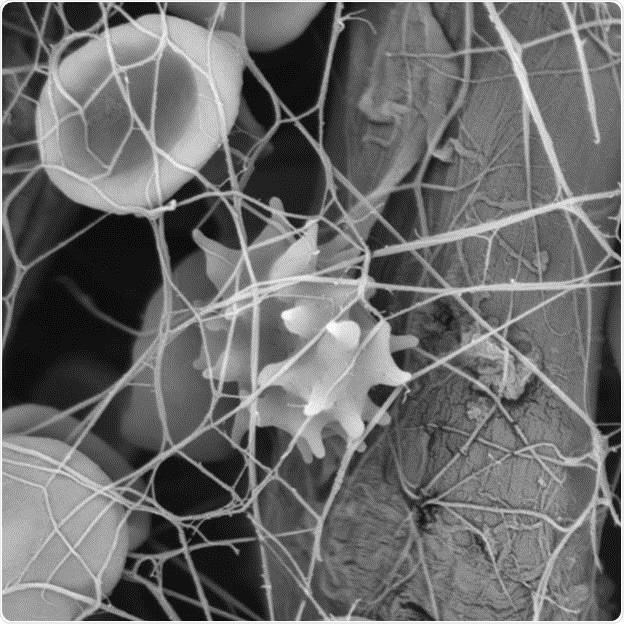

Figure 1: Each wounding causes a reaction by the body- This is the example of a fibrin network with blood cells images with scanning electron microscopy.

Blood disorders are a different class of blood diseases that occur due to insufficient blood clotting caused by lack of thrombocytes or other components involved in the blood clotting process. In case of an injury, in normal conditions, clotting factors and fibrin present in the blood allow binding of thrombocytes with each other to form a plug at the affected site to avoid further hemorrhage and facilitate healing of the injured tissue.

Blood research has turned out to be an increasingly popular research field to gain insights into the interactions taking place during clot formation. For this purpose, the SEM has been shown to be very useful, enabling scientists to easily observe the 3D structures of blood clots and the interactions taking place between the blood cells and different fibers.